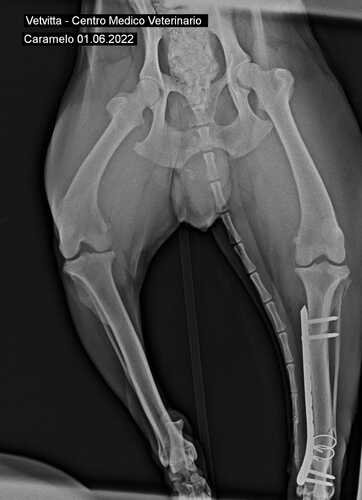

Levamos então para a Clínica Veterinária VetVitta, onde o Dr. Fábio, cirurgião e ortopedista, cuidou prontamente do Caramelo. Foram muito generosos e nos deram descontos no procedimento cirúrgico, não cobraram nem consulta nem internamento. O valor da cirurgia, incluindo medicamentos e radiografias, ficou em R$1870. Compramos também um antipulgas, porque ele estava infestado, totalizando os R$1935,50, que consta no extrato abaixo.

Radiografias Depois